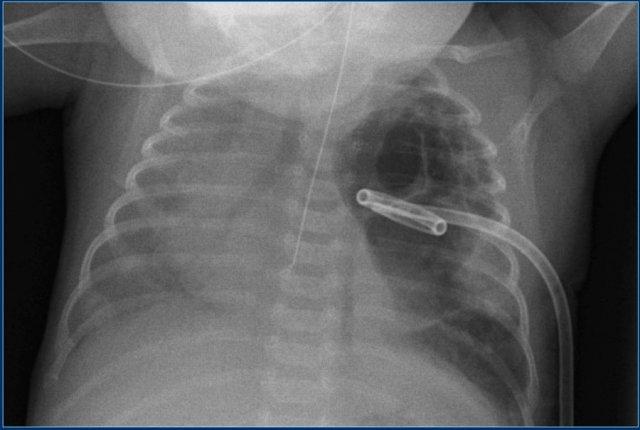

Ống dẫn lưu ngực

Ống dẫn lưu ngực được đặt trong trường hợp suy hô hấp do tràn dịch màng phổi hoặc tràn khí màng phổi, nhằm đảm bảo phổi giãn nở đủ để thông khí.

Ống nên được đặt tại đường nách giữa, qua khoang liên sườn thứ 4 – 6.

Vị trí đặt ống nên ở phía trước-đỉnh phổi đối với bệnh nhân tràn khí màng phổi.

Quan sát hình ảnh.

Các phát hiện bao gồm:

- Ống nội khí quản ở vị trí tốt.

- Ống dẫn lưu ngực thẳng ở vị trí tốt. Tuy nhiên, hiệu quả dẫn lưu chưa tối ưu.

- Trung thất lệch sang phải. Tuy nhiên không có tràn khí màng phổi áp lực, vì cơ hoành vẫn có bờ trên lồi bình thường.

Ở bệnh nhân này, có một nang khí phổi (pneumatocele) lớn, một catheter đuôi lợn (pigtail catheter) đã được đặt vào trong nang khí.